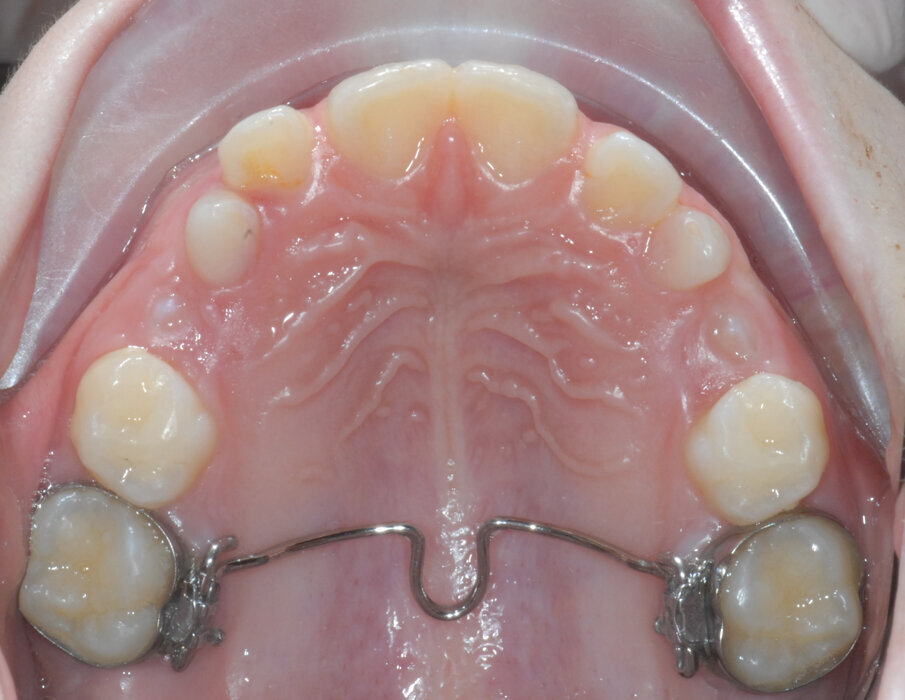

Dopo aver rilevato delle impronte con polivinilsilossano per realizzare un espansore del palato, si esegue l’espansione rapida del mascellare (Figg. 5, 6) superiore con il dispositivo cementato sui secondi molari decidui (5.5-6.5). Al termine dell’espansione, sono rilevate delle nuove impronte con polivinilsilossano per realizzare una barra palatale (Fig. 6) ancorata sui primi molari permanenti (1.6-2.6); viene eseguito un protocollo di estrazioni anticipate dei primi molari decidui e dei canini decidui (Figg. 7-9).

Fig. 5_Espansore rapido del palato ancorato su “E”.

Fig. 6_Termine dell’espansione.

Fig. 7_Barra palatale, exo “D” ed eruzione 1.4-2.4.